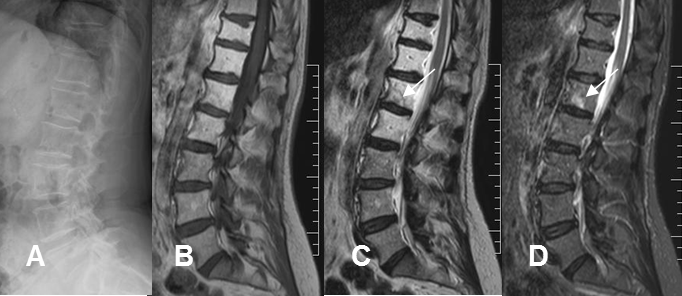

Fig 17 B. Reconversión a medula amarilla.

A: Rx lateral. Signos de osteopenia generalizada.

B: RM sagital en T1, C: RM sagital en T2 y D: RM sagital en STIR. Los cuerpos de D11 a L2 tienen alteración de su señal, con predominio de medula ósea amarilla. El paciente tiene antecedente de un ampuloma y los cambios corresponden a radioterapia. En la placa terminal inferior de L1 existe imagen hiperintensa en T2 y STIR, (Flecha), por proceso degenerativo.